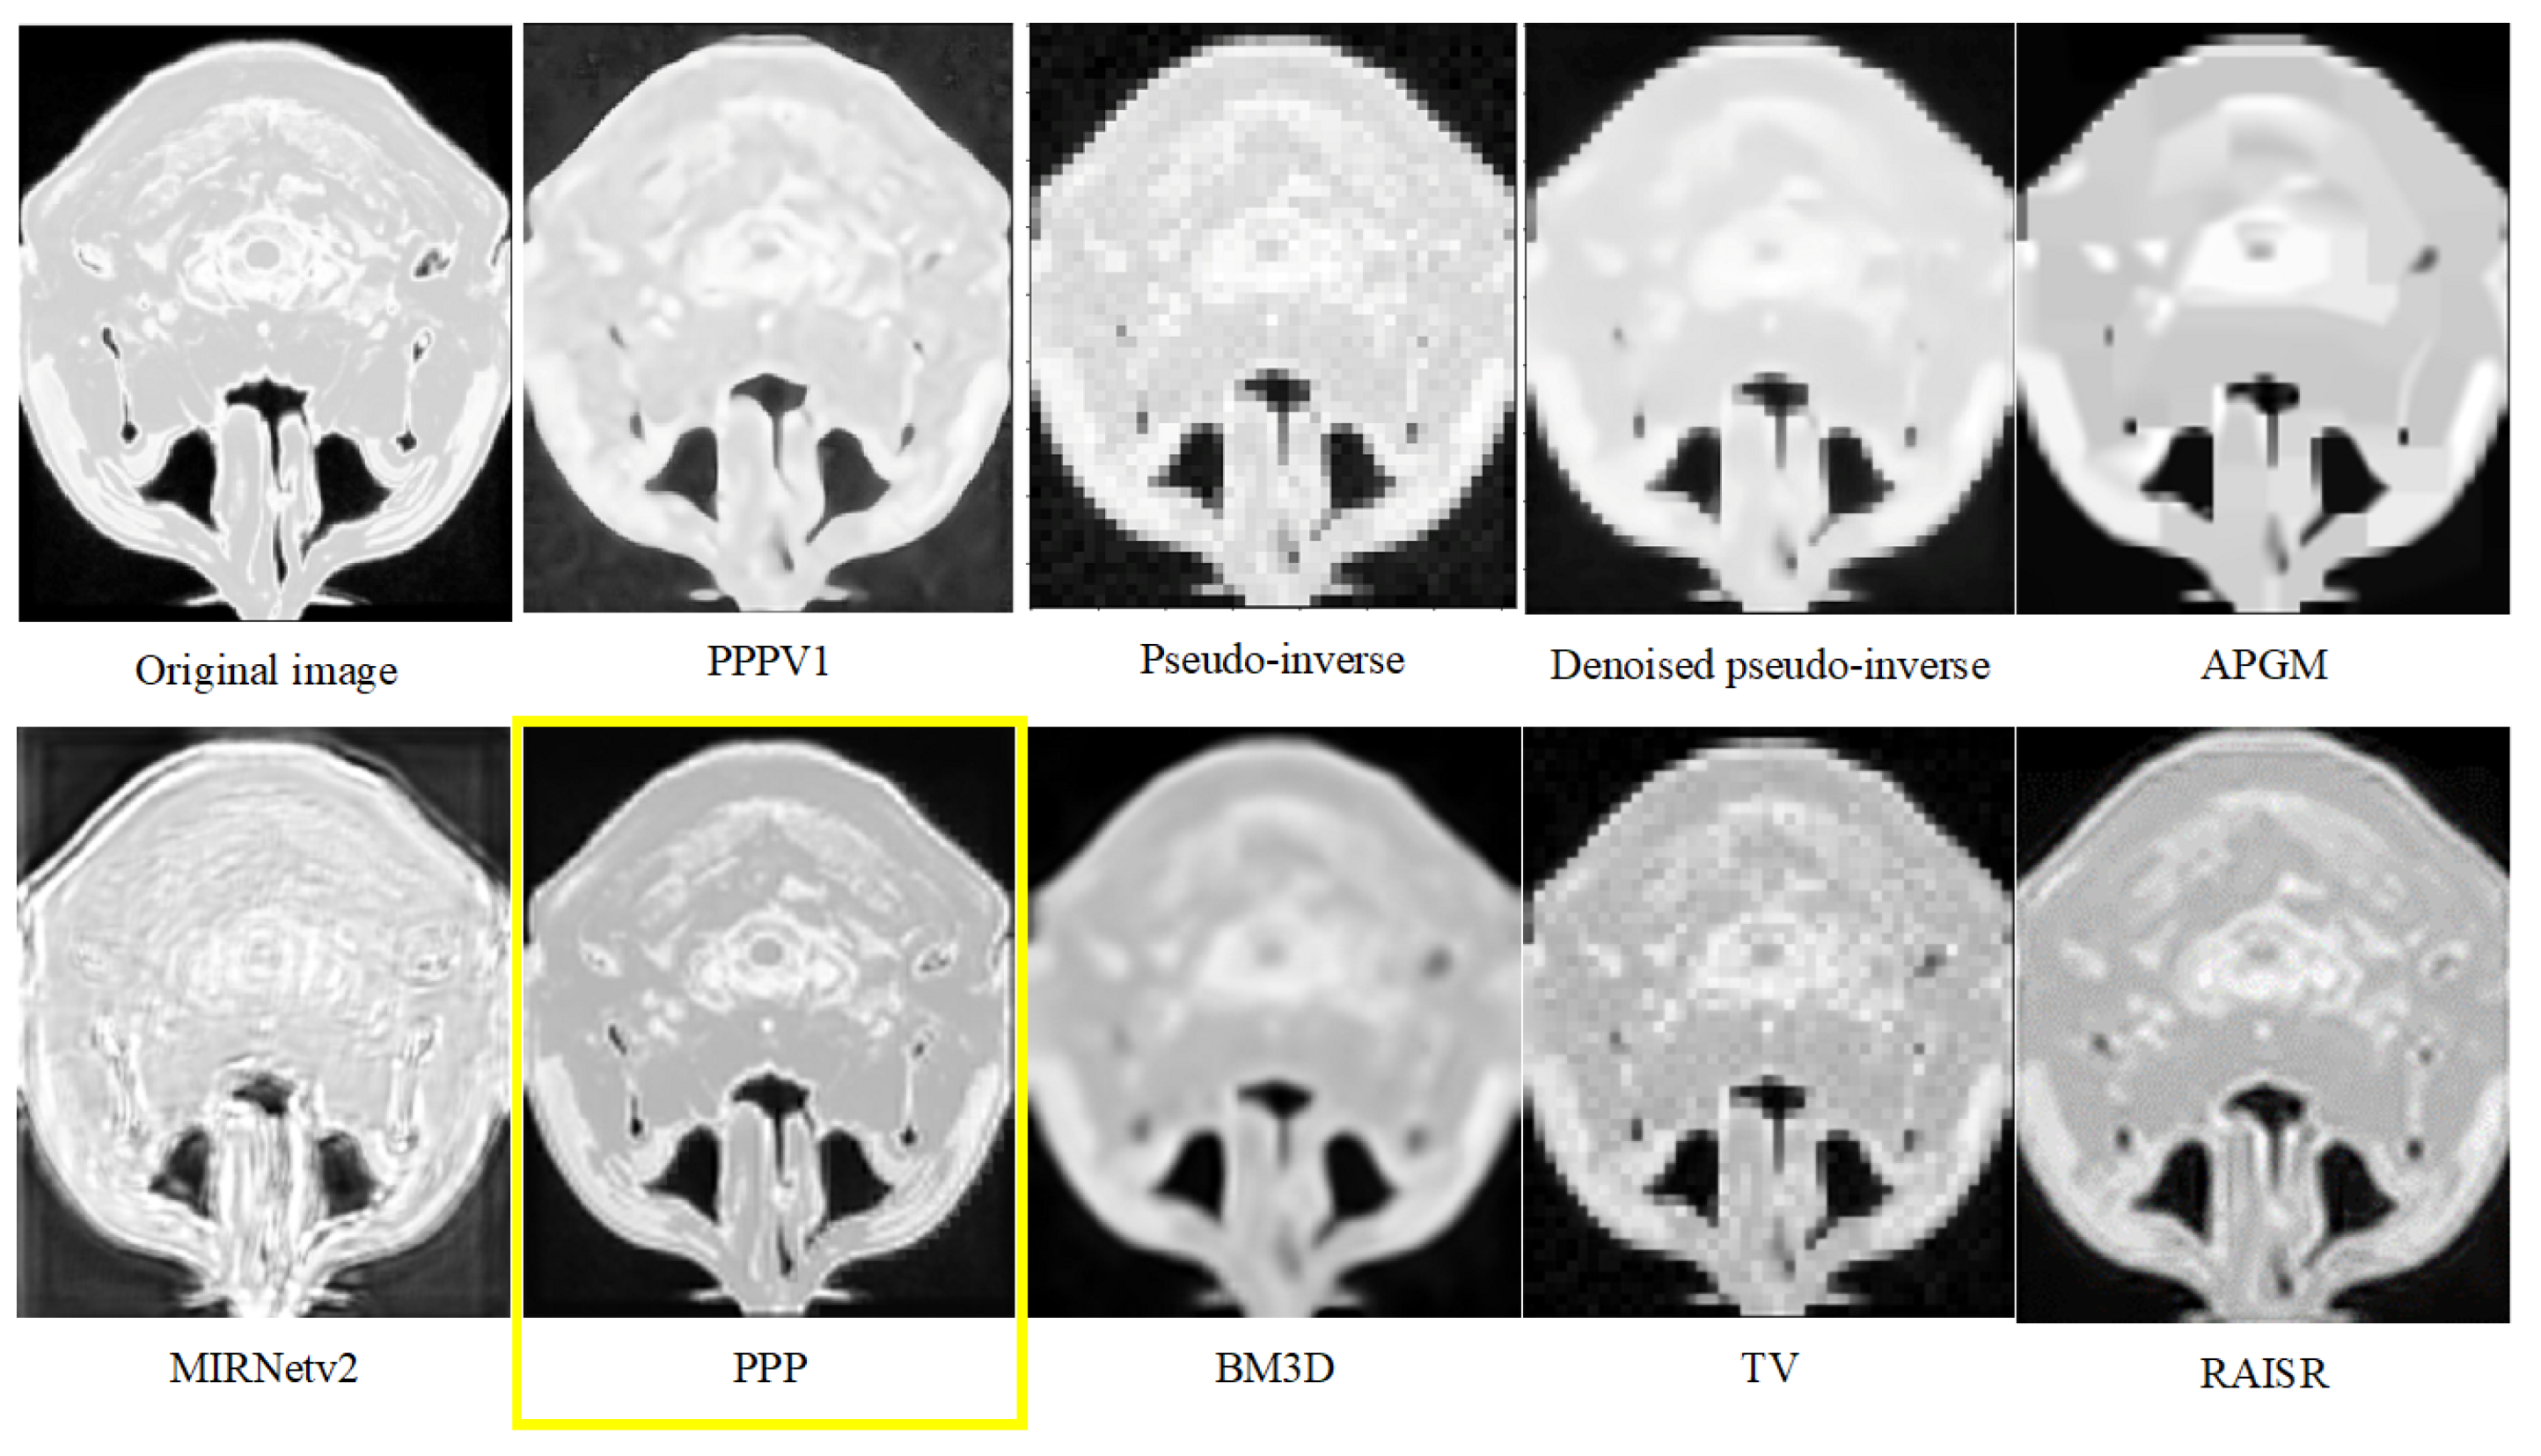

| Dataset 1 | Dataset 2 | |||

|---|---|---|---|---|

| Average | St.Dev | Average | St.Dev | |

| PPPV1 | 22.49 | 0.44 | 25.26 | 0.25 |

| Pseudo-inverse | 19.52 | 0.56 | 22.81 | 0.26 |

| Denoised pseudo-inverse | 20.36 | 0.51 | 23.73 | 0.28 |

| APGM | 19.91 | 0.34 | 23.78 | 0.22 |

| MIRNetv2 | 14.05 | 0.27 | 14.26 | 0.18 |

| PPP | 26.59 | 0.49 | 25.67 | 0.65 |

| BM3D | 20.58 | 0.82 | 23.72 | 0.36 |

| TV | 22.48 | 0.44 | 23.50 | 0.29 |

| RAISR | 21.99 | 0.43 | 25.77 | 0.32 |